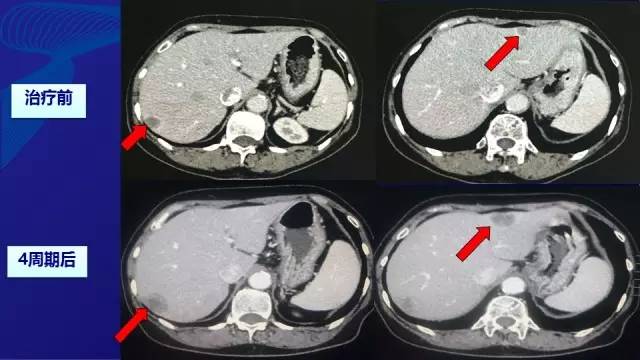

● 2周期—SD; 4周期—PD

● 由于经济原因拒绝使用靶向药物,予XELOX方案化疗(减量) –奥沙利铂:100 mg/m2, d1 –卡培他滨:850 mg/m2,BID, d1-d14。无严重不良反应。